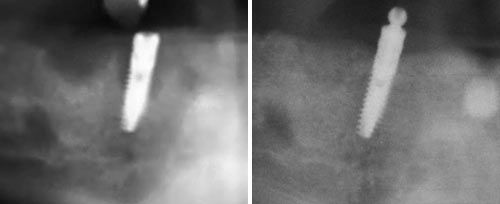

Periimplantitis Treatment

Courtesy of: Ilay Maden Ph.D., M.Sc.

Laser source: Er:YAG (2940 nm)